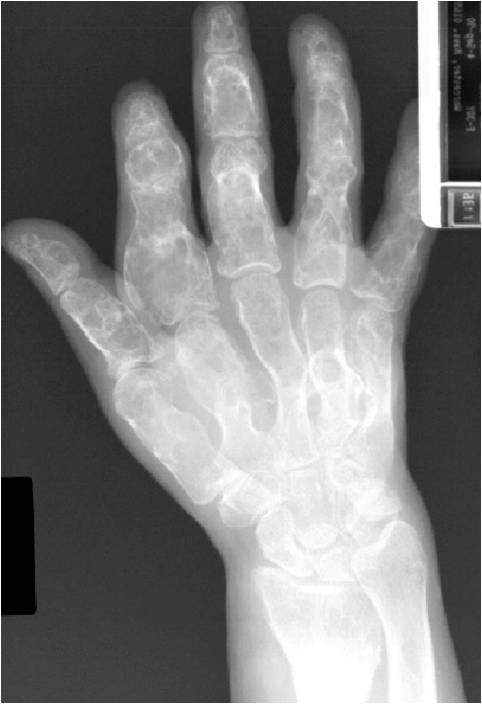

- 50% involve hands and feet (mostly phalanges)

- Localized, radiolucent defect usually with punctate calcifications

- Calcifications are typical but not always present

- Matrix may demonstrate various degrees of calcification

- Calcifications are stippled, punctate, popcorn like calcifications and “Ring and Arc” calcifications

- Cartilage tumors grow in a lobular manner. The perimeters of the lobules undergo

- enchondral ossification that may calcify. If the entire perimeter of the lobule calcifies it appears

- radiographically as a “Ring”. If a portion of the perimeter of a lobule calcifies it forms an “Arc” on

- an X-ray.

- Grows eccentrically or concentrically (phalanges)

- Cortex may be scalloped and thinned in the phalanges

- Geographic lytic lesion

- Central often metaphyseal in long bones

- Expansile remodeling with thinned cortex

- Chondroid matrix with calcifications in majority of tumors

- Approximately 20% have limited or no calcifications